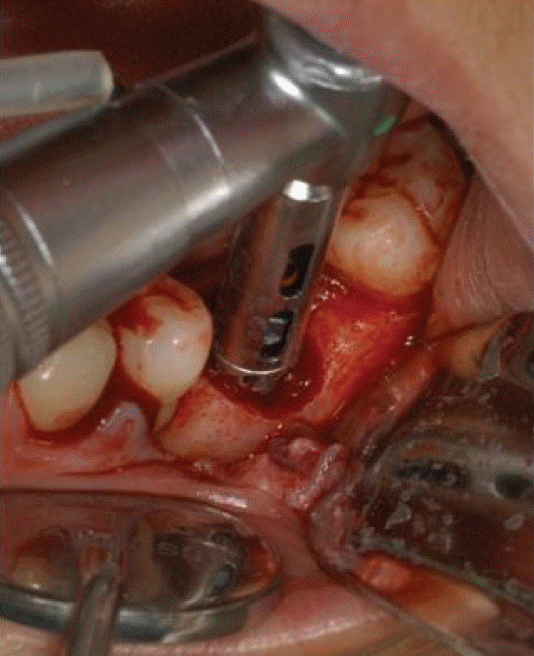

모든 치주진료는 치석제거술이 먼저 시행되어야한다. 임플란트 8주위염도 마찮가지이다. 반드시 본원에서 시행될 필요는 없으며 최근에 타원에서 시행된 경우에는 내역설명이 필요하다. 이미 보철이 진행된 곳에 환형의 치조골소실이 발생된 경우에(Fig. 8) 치석제거와 함께 보철을 제거하고 cover screw 를 연결해주면 연조직이 치유된다(Fig. 9). 이후에 치조골결손부골이식술을 시행하고(Fig. 10) 일정기간 치유가 이루어진 후 다시 임플란트를 노출(치은박리소파술 적용)하여 치유지대주를 연결하고 재보철을 함으로서 임플란트를 재생하여 다시 사용해볼 수 있는 술식을 건강보험항목으로 진행할 수 있다.